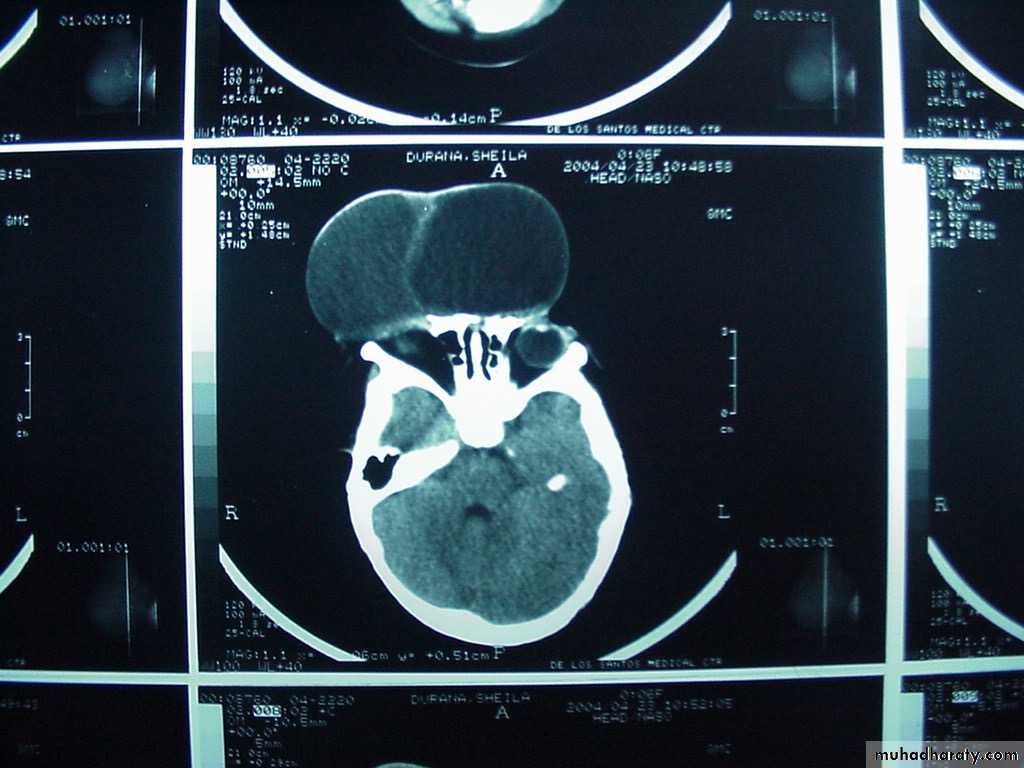

P.M, 22 days old CA 36-37 wks, with cleft lip and palate

Holoprosencephaly, semilobarMacrogyria

Absent Septum Pellucidum

Dysgenesis of the Corpus Callosum